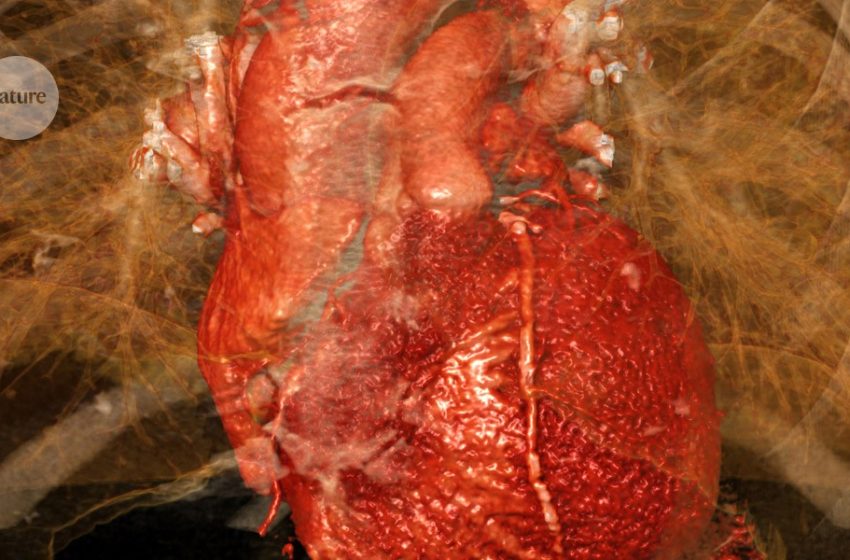

Heart damage caused by a myocardial infarction is exacerbated by activation of a heart–brain–immune axis.Credit: Sevolod Zviryk/Science Photo Library